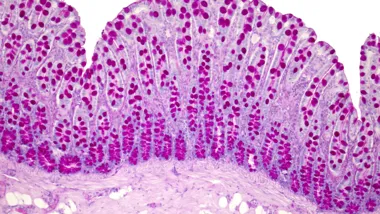

Natalie received her Ph.D. in Human Molecular Genetics from the UCL Institute of Child Health in 2000 and remained there to do her first postdoc on the complex genetics of cleft lip and palate. In 2001 she was awarded a UCL Bogue visiting fellowship to the McKusick-Nathans Institute of Genetic Medicine, John’s Hopkins, Baltimore, Maryland USA. She joined the Department of Medical and Molecular Genetics at King's in 2004 as a postdoc in Prof Chris Mathew’s lab investigating the genetic etiology of the inflammatory bowel diseases (IBD)’ Crohn’s disease (CD) and ulcerative colitis (UC).

In 2011 she received the prestigious Wellcome Trust University Award, a five-year Career Development Fellowship to begin her own independent research program investigating the functional importance of non-coding genome regions that have been strongly implicated in IBD through genome-wide association studies (GWAS). In 2017 she became a Lecturer in the Department of Medical and Molecular Genetics, King's. Her research interests include exploring the functional significance of genetic variations associated with IBD and orofacial granulomatosis (OFG).

The IBD and Complex Genetics Group is led by Dr Natalie Prescott that conducts research on inflammatory bowel disease.